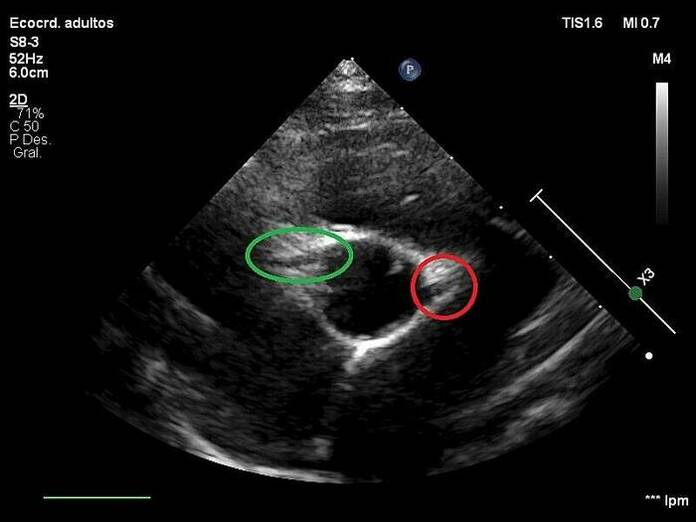

El modelo propuesto por los investigadores aborda el primer paso de análisis automático del ecocardiograma: la detección de las arterias coronarias en los fotogramas del mismo. “En esta primera etapa, el sistema extrae todos los fotogramas pertenecientes al ecocardiograma y se clasifican en función de las arterias que aparecen en ellos: arteria izquierda, arteria derecha, ambas arterias o ninguna”, ha añadido el científico.